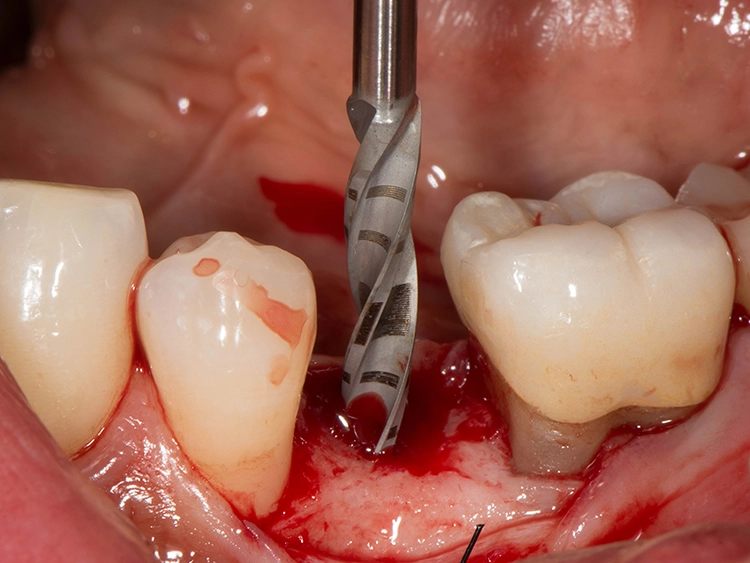

Sie bieten Vorteile, „wenn gleichzeitig eine Knochenaugmentation geplant ist und das Implantat nicht mit einer hohen Primärstabilität inseriert werden kann. Das kann im Frontzahnbereich sein, wenn eine laterale Knochenaugmentation erfolgen soll. Das gilt aber ebenso für den Seitenzahnbereich, wenn gleichzeitig ein Sinuslift durchgeführt wird, wo wir Höhe aufbauen und wir eine unerwartete Überbelastung verhindern wollen“, beschreibt der erfahrene Oralchirurg und erklärt: „Dann sind zweiteilige Implantate einfacher in der Anwendung, weil das Abutment nicht in die Mundhöhle hineinragt und daher eine ungewollte frühzeitige Belastung verhindert werden kann. Außerdem stellen zweiteilige Implantate bei zahnlosen Patienten eine verlässliche Option dar.“

Zweiteilige Implantatsysteme würden darüber hinaus mit einer höheren prothetischen Flexibilität punkten, weil die Aufbauten individueller gestaltet werden können. Dr. Röhling: „Das kann ein Vorteil sein, wenn etwa die prothetische Achse korrigiert werden muss.“ Hinzu kommt, dass bei Anwendung von zweiteiligen Systemen eine Zementierung, die für Fehlerquelle anfällig gesehen wird, entfällt, da sie eine reversibel verschraubte Befestigung erlauben, während bei einteiligen Implantaten die Suprakonstruktion nur zementiert gestaltet werden kann (siehe Fallbeispiel, Abbildungen 1 bis 10).